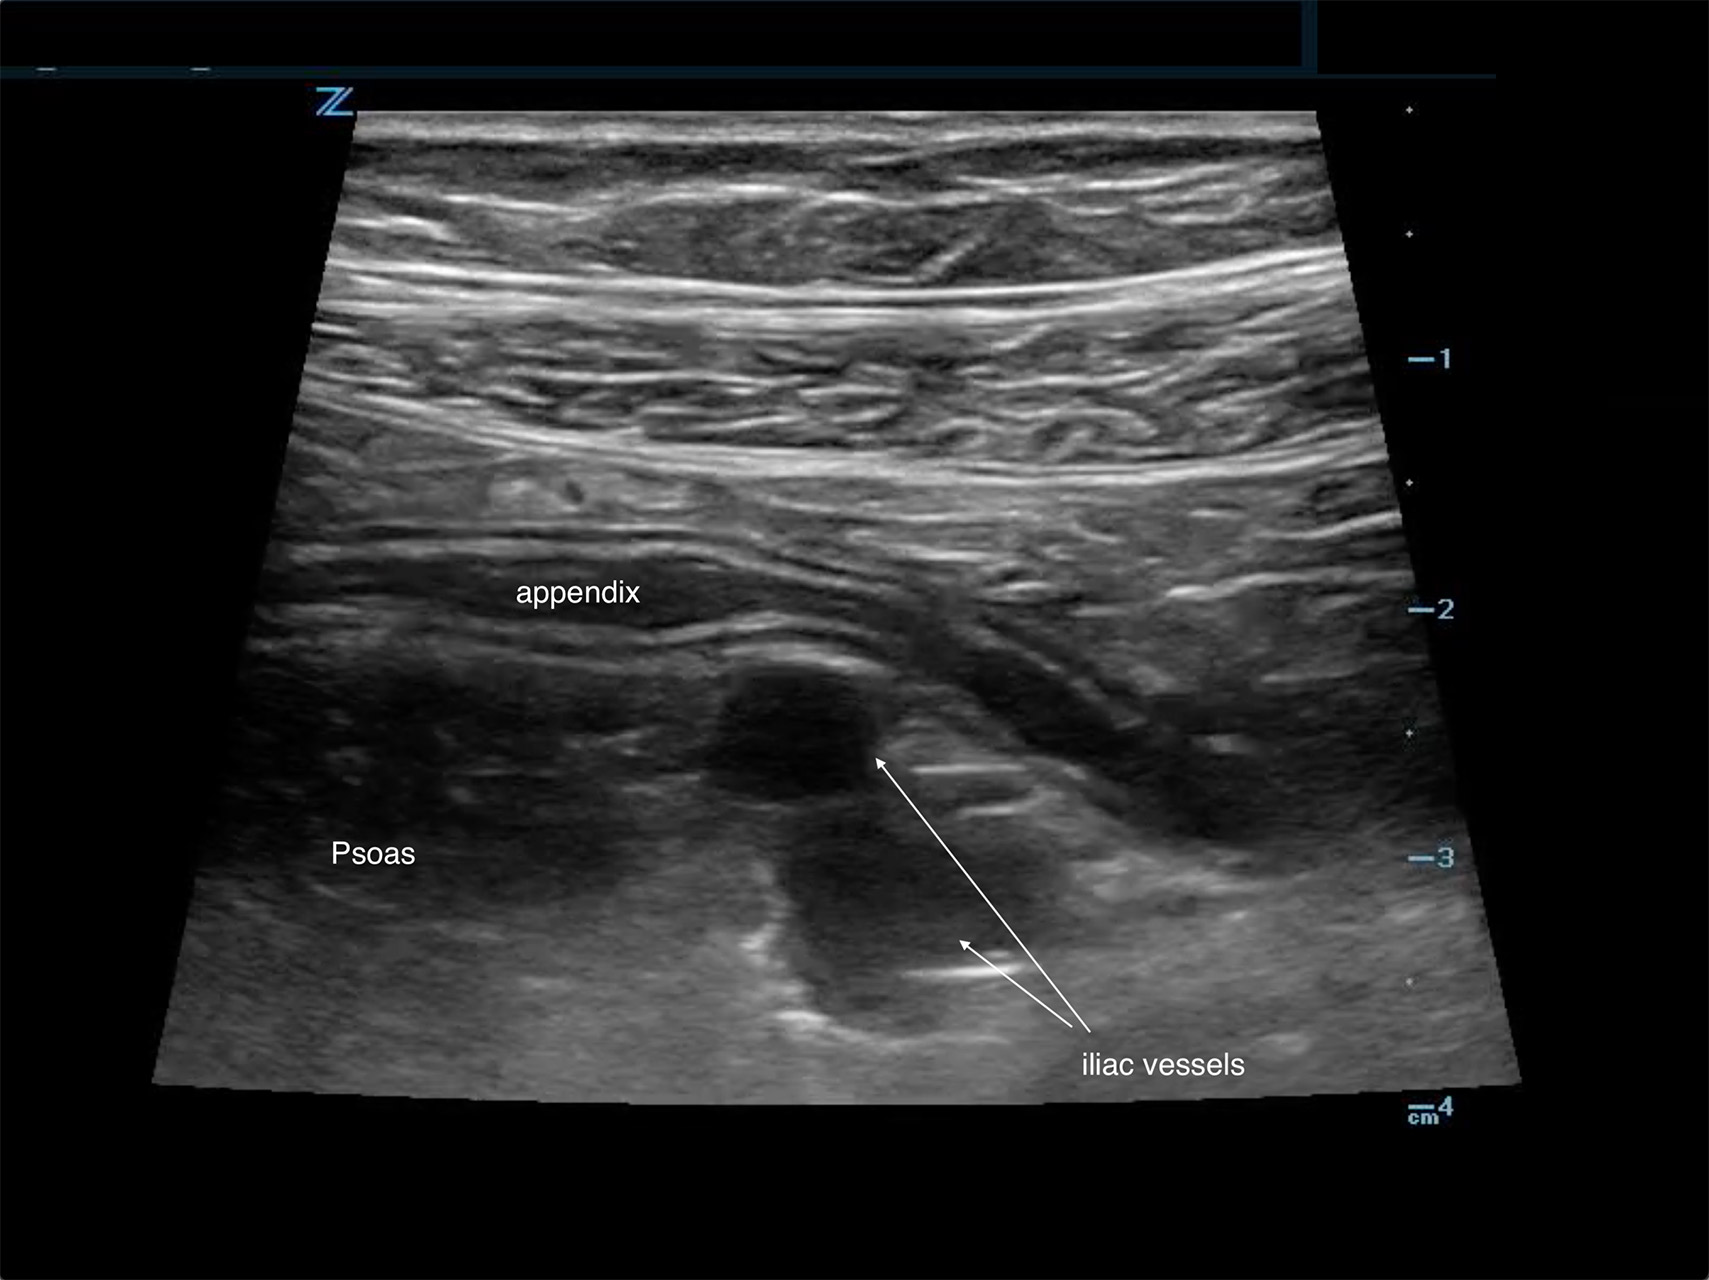

When scanning in the right lower quadrant, the two landmarks that are used to help identify the appendix are the psoas muscle and the iliac vessels (Figure 1).

Figure 1. Typical location of the appendix anterior to both the psoas and iliac vessels

- Localize the landmarks in the right lower quadrant. Identify the psoas muscle and the iliac vessels.

- Localize the appendix, which is typically anterior to the psoas and iliac vessels (Figure 1).